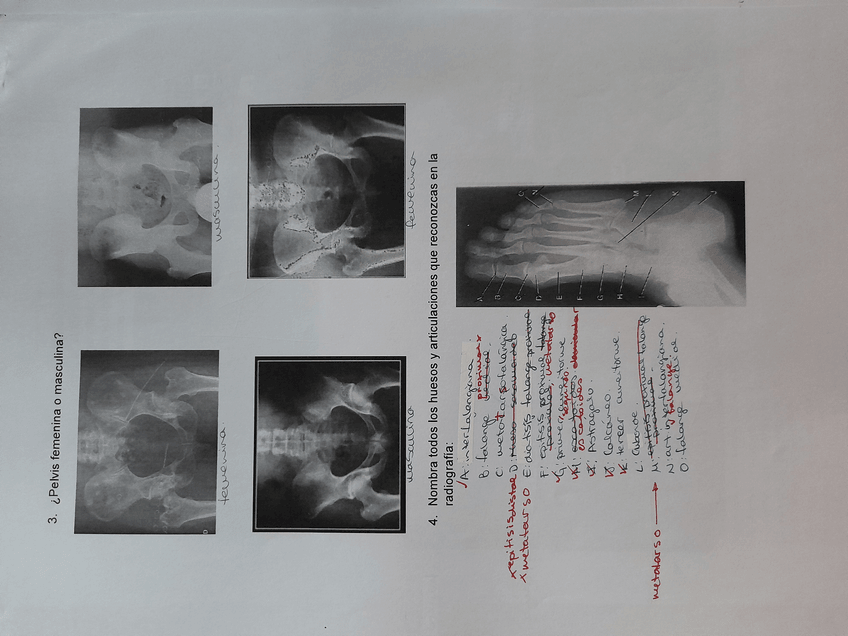

ANATOMIA

Columna, cintura, extremidades…